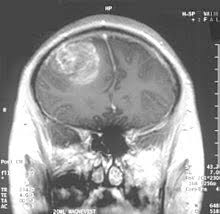

Es ist eine art barriere die aus zellen besteht, die eng miteinander verschränkt sind, so dass nichts aus den blutgefäßen entweichen und ins gehirn eindringen kann. Ausgangserkrankungen, wie diabetes mellitus, entzündungen im gehirn oder hirntumoren, schädigen häufig diese barriere. Jahrhunderts vom deutschen bakteriologen paul ehrlich entdeckt. Seine hauptaufgabe besteht darin, als selektiver (semipermeabler) filter zu wirken, der nur bestimmte moleküle durchlässt, während andere zur richtigen zeit blockiert werden. So bleibt die homöostase im gehirn erhalten. So wäre es dem wiener forscher zufolge durchaus denkbar, die pumpenblockade bei besonders schweren fällen von epilepsie anzuwenden. Hauptbe­standteil dieser schranke sind endothelzellen. Für das gehirn können auch zellen des eigenen immunsystems sowie botenstoffe des immunsystems schädlich sein.

So wäre es dem wiener forscher zufolge durchaus denkbar, die pumpenblockade bei besonders schweren fällen von epilepsie anzuwenden. Ausgangserkrankungen, wie diabetes mellitus, entzündungen im gehirn oder hirntumoren, schädigen häufig diese barriere. Veränderungen ihrer permeabilität (durchlässigkeit) können dazu führen, dass krankheitserreger und toxische stoffe leichter ins gehirn eindringen und dass hirnödeme (anschwellung des gewebes durch flüssigkeitsansammlung) verursacht werden, die je nach ausmass zu einem anstieg des hirndrucks mit daraus resultierenden durchblutungsstörungen führen. Sie ist durchlässig für nährstoffe, so dass das gehirn mit allem was es braucht, versorgt ist. Sie können diesen filter nicht passieren. So bleibt die homöostase im gehirn erhalten. Isolierte schrankenstörungen treten im rahmen verschiedener netzhauterkrankungen auf: Bei diabetischer retinopathie ) der funktionsverlust der äußeren brs wird als pathomechanismus der retinopathia centralis serosa diskutiert.